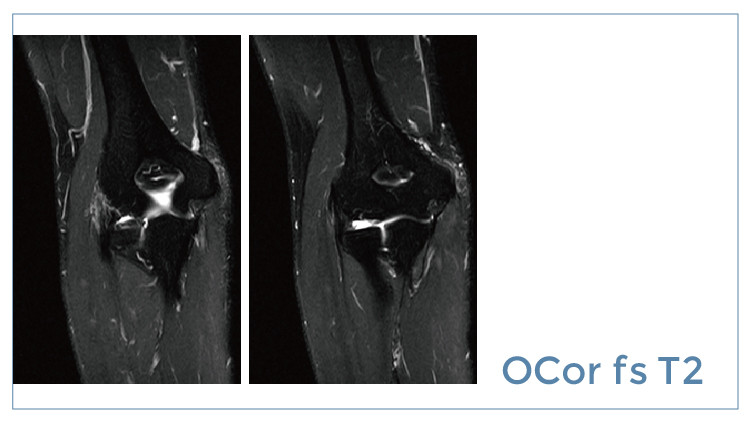

【朗润影像档案】20190719磁共振影像病例结果讨论

【朗润影像档案】磁共振影像病例分享(编号20190719)